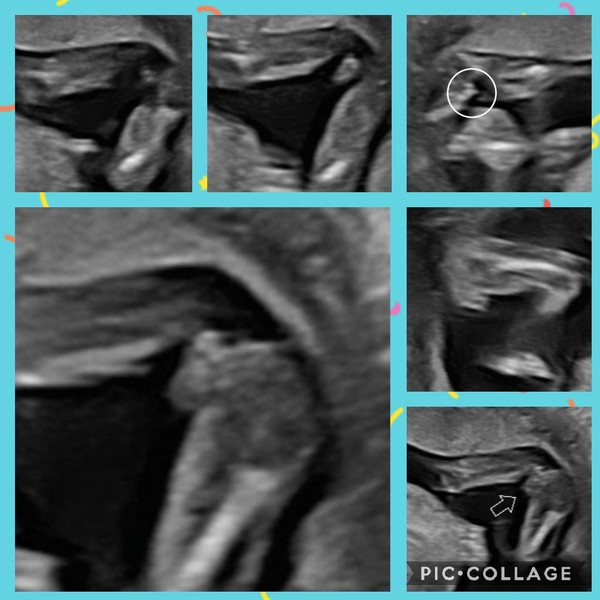

@HistoriaTrixie Hi, what do you think of mine please.. would really appreciate your opinion..

All images are from exactly 15 weeks...

Potty shot..

MamaJ8 · 14/03/2021 20:47

I also have think that there is a shape that looks like a scrotum and looks similar to OP's?

What do you think?😊